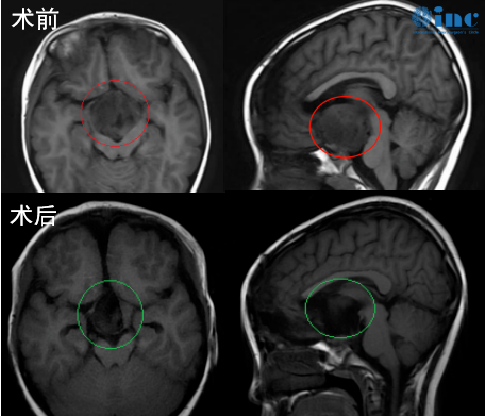

治疗过程:后求诊于INC国际神经外科教授,在巴教授主刀下完成了保神经、近全切的手术效果(切除率达到了95%以上),手术结束后一个小时左右苏醒。当天就转到普通病房,术后MR显示肿瘤近全切(95%以上)。术后巴教授去病房查房,孩子对答如流,视力得以保留。悦悦父母终于可以放下心来,孩子都很好,可爱活泼、充满神采,生活都慢慢步入正轨。